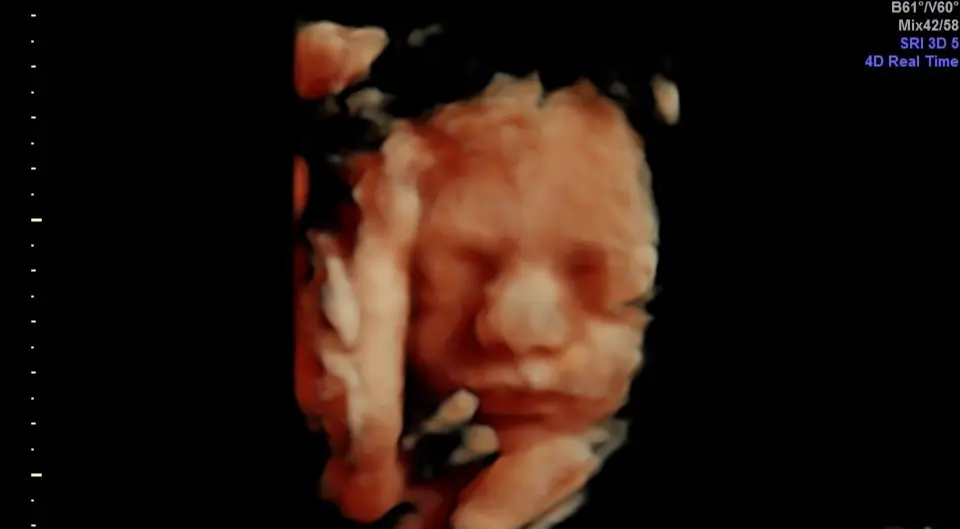

At Samagra Care, our advanced 3D and 4D ultrasound services provide a unique opportunity for expecting parents in Bhopal to connect with their unborn baby. Unlike traditional 2D scans, which produce flat, grey-scale images, our 3D and 4D ultrasounds let you see your baby in incredible depth and detail, offering a true-to-life view of your baby’s skin, facial features, and movements.

With a 3D ultrasound, you can enjoy a three-dimensional image created by combining multiple two-dimensional images taken from various angles. This technology allows you to see your baby's face and surface details, making it feel like you're looking at a real photo.

Our 4D ultrasound takes this experience one step further, providing a live video so you can watch as your baby yawns, stretches, or kicks. It’s an incredible way for families to bond with their baby before birth and capture precious moments in the womb.